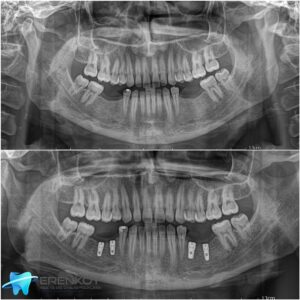

Diş implantı